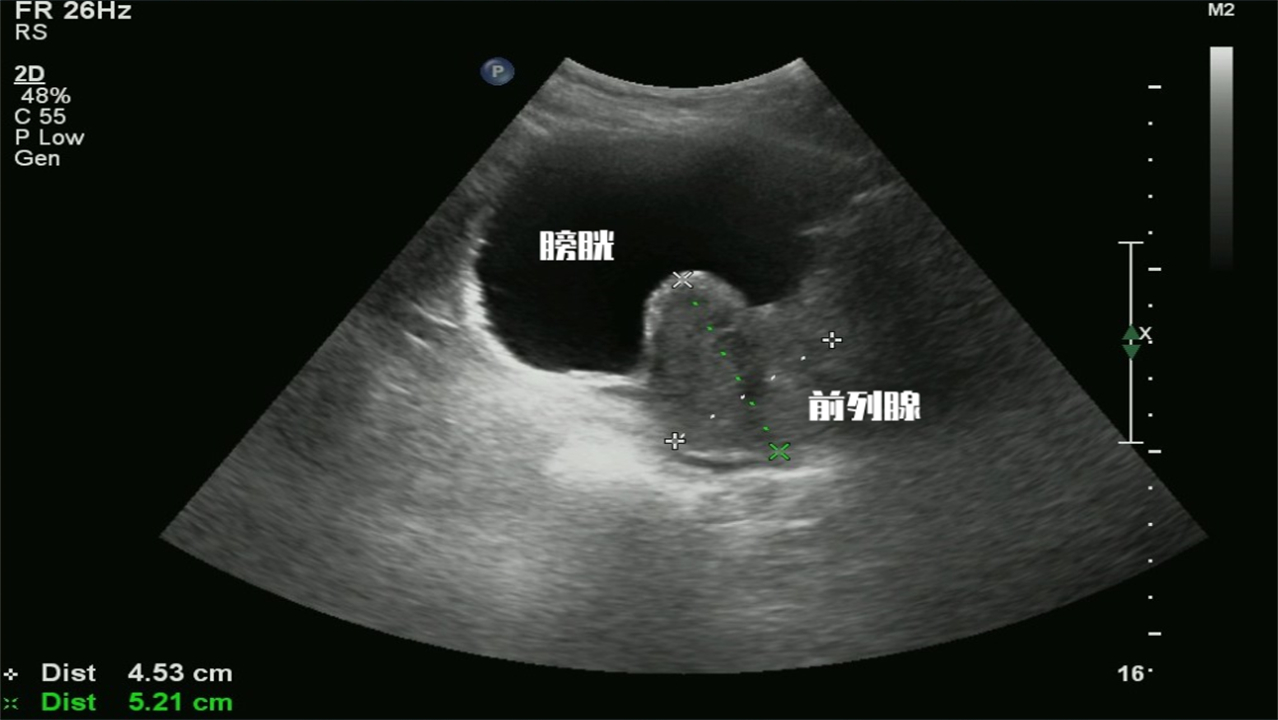

前列腺的正常大小一般在4cm*3cm*2cm,若是大家检查结果上的数值是大于正常值,说明前列腺变大了,需要警惕是否是前列腺增生引起的。

大家若是发现前列腺增生的方向是向膀胱内凸出的,那么很大概率就可以确诊为前列腺增生,并且情况还比较严重,此时需要及时进行医治。

因为前列腺增生主要以中叶增生、两侧叶增生为主,而膀胱的压力比较低,当前列腺增生比较明显时,就会向旁观凸出。

并且由于膀胱内出现了部分前列腺的组成部分,还可能会导致膀胱阻梗,引起尿频、尿急、尿*禁失**等不良症状。对于存在上述尿*禁失**、膀胱阻梗等人群而言,残余尿量的数值大于50毫升的检查结果可以说是经常看见的。